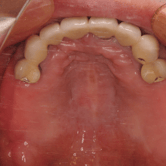

Edentulismo total

Ausencia completa de dientes en una o ambas arcadas, comprometiendo gravemente la masticación y la estética facial.

La falta de dientes también puede causar atrofia ósea acelerada en las mandíbulas.

Los pacientes pueden experimentar dificultades significativas para hablar y comer. Además, la falta de soporte dental puede provocar un aspecto facial envejecido.